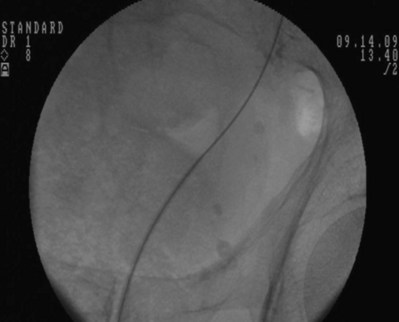

An alternative technique that relies more on fluoroscopic visualization for stent placement and less on cystoscopic visualization is often advantageous when dealing with more challenging stent placements such as impacted ureteral stones or malignant obstruction (Figs. 7-7 through 7-16).

Figure 7–9 The 8 portion has been removed. Asterisk shows the faint outline of the 10 portion along the guidewire.

After obtaining bladder access with either a flexible or rigid cystoscope, a floppy-tip guidewire is advanced into the ureteral meatus and coiled in the renal pelvis using fluoroscopy, the cystoscope is then removed and an 8- to 10-Fr coaxial dilator is advanced under fluoroscopy until the 10-Fr sheath is at the urethral meatus. The 8-Fr internal dilator is removed, leaving a conduit (10-Fr outer sheath) through which to advance the stent.

The ureteral stent is then advanced over the guidewire through the 10-Fr sheath by using a pusher with a small fluoroscopically visible metal band at its tip. The metal tip pusher is advanced under fluoroscopic control to the upper border of the pubic symphysis in male patients and lower border in female patients, while stabilizing the position of the lower end of the stent. The 10-Fr sheath and subsequently the guidewire are removed, allowing the stent to curl in the bladder.